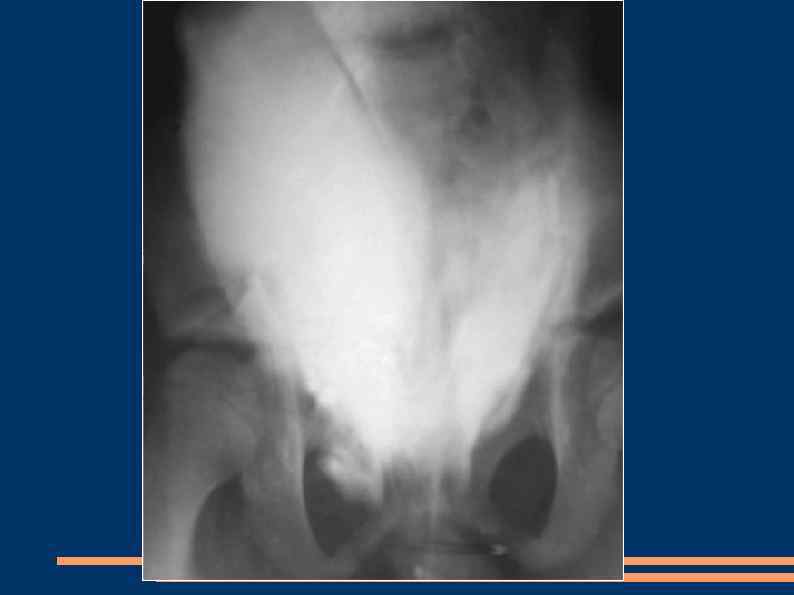

Внутрибрюшинный разрыв мочевого пузыря Гематурия В надлобковой области может определяться инфильтрат Клиника перитонита Тяжелая итоксикация Диагностика: ретроградная цистография Лечение: нижняя лапаротомия, аспирация мочи и крови из брюшной полости, ушивание стенки двухрядным швом, не захватывая в швы слизистую оболочку (наличие лигатур в просвете мочевого пузыря ведет к формированию конкрементов). Дренирование мочевого пузыря